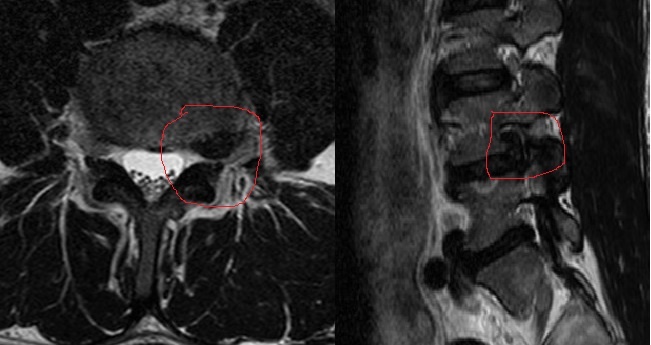

Тот же пациент, отснятый примерно через полгода. На саггитальном срезе хорошо видно, как освободилось фораминарное отверстие.